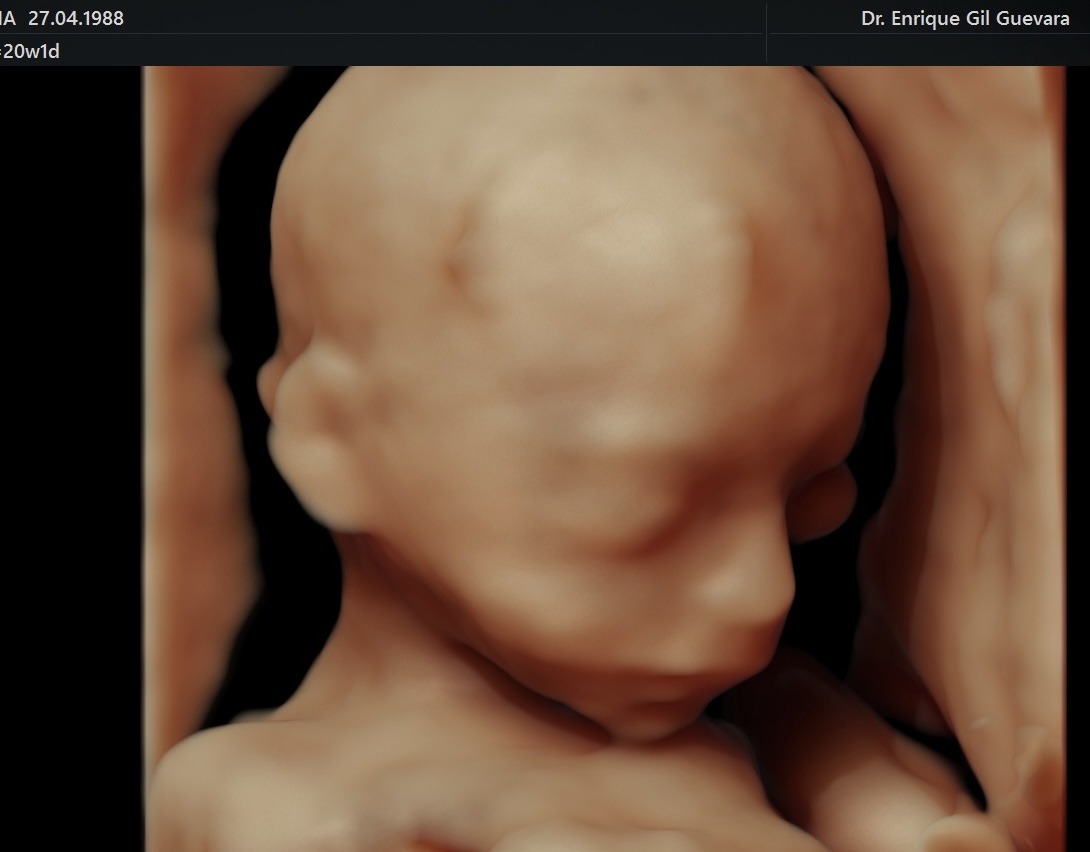

– Ecografía en HD Live Resolution (5D/7D).

– Ecografía en HD Live Resolution (5D/7D).

– Ecografía en HD Live Resolution (5D/7D).

– Ecografía en HD Live Resolution (5D/7D).

– Ecografía en HD Live Resolution (5D/7D).

– Ecografía en HD Live Resolution (5D/7D).

– Ecografía en HD Live Resolution (5D/7D).

– Ecografía en HD Live Resolution (5D/7D).

– Ecografía en HD Live Resolution (5D/7D).

– Ecografía en HD Live Resolution (5D/7D).

– Ecografía en HD Live Resolution (5D/7D).

– Ecografía en HD Live Resolution (5D/7D).

– Ecografía en HD Live Resolution (5D/7D).

– Ecografía en HD Live Resolution (5D/7D).

– Ecografía en HD Live Resolution (5D/7D).

– Ecografía en HD Live Resolution (5D/7D).

– Ecografía en HD Live Resolution (5D/7D).

– Ecografía en HD Live Resolution (5D/7D).

– Ecografía en HD Live Resolution (5D/7D).

– Ecografía en HD Live Resolution (5D/7D).

– Ecografía en HD Live Resolution (5D/7D).

– Ecografía en HD Live Resolution (5D/7D).

– Ecografía en HD Live Resolution (5D/7D).

– Ecografía en HD Live Resolution (5D/7D).

– Ecografía en HD Live Resolution (5D/7D).

– Ecografía en HD Live Resolution (5D/7D).

– Ecografía en HD Live Resolution (5D/7D).

– Ecografía en HD Live Resolution (5D/7D).

– Ecografía en HD Live Resolution (5D/7D).

– Ecografía en HD Live Resolution (5D/7D).